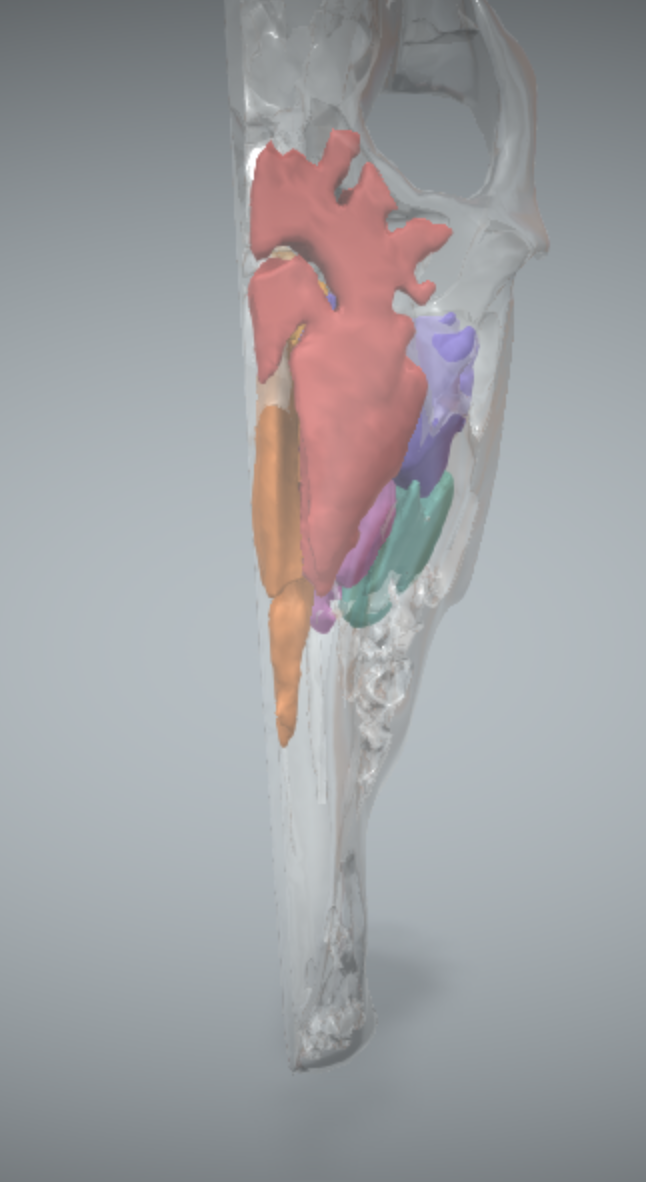

name the sinuses

pink: ventral conchal sinus

yellow: sphenopalatine sinus

light blue: rostral maxillary sinus (left)

purple: caudal maxillary sinus

red: frontal sinus

orange: dorsal conchal sinus